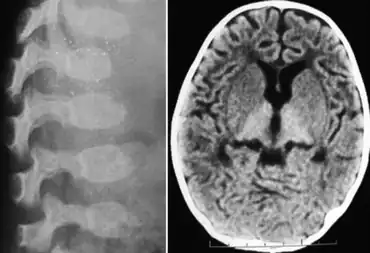

GM1 gangliosidosis-X-ray indicates dysostosis multiplex at lumbar region and scan of brain indicates hyperdense thalamus

• Skeletal deformities: flexion contractures noted by 3 months; early subperiosteal bone formation (may be present at birth); diaphyseal widening later; demineralization; thoracolumbar vertebral hypoplasia and beaking at age 3–6 months; kyphoscoliosis. *Dysostosis multiplex (as in the mucopolysaccharidoses)